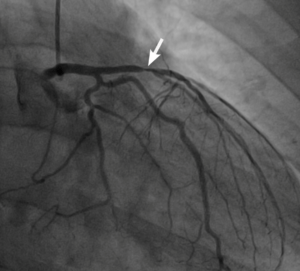

John wouldn’t stand out as one who might be at high cardiovascular risk. He’s in his early forties, keeps a fairly healthy diet, and participates in triathlons. And yet, he also has a 90% blockage in his left anterior descending artery (LAD), a major coronary artery long known as the “widow-maker.”

Figure: Imaging revealed near-complete blockage (indicated by arrow) of the “widow-maker” left anterior descending artery.

John was a time-bomb, and in all likelihood, he had little left on the clock. But thanks to his own initiative, he was able to change the course of his story. Based on information he’d gathered from The Drive, he set out to obtain a better picture of his coronary health by requesting tests for apolipoprotein B (apoB), and Lp(a) – neither of which are included in typical lipid panels. Lo and behold, both were elevated, with Lp(a) in particular reaching the level of very high risk. After a coronary artery calcium (CAC) scan raised further red flags, John saw a cardiologist, who ordered a computed tomography angiogram (CTA) that confirmed the grim reality: severe stenosis (narrowing) of the LAD.